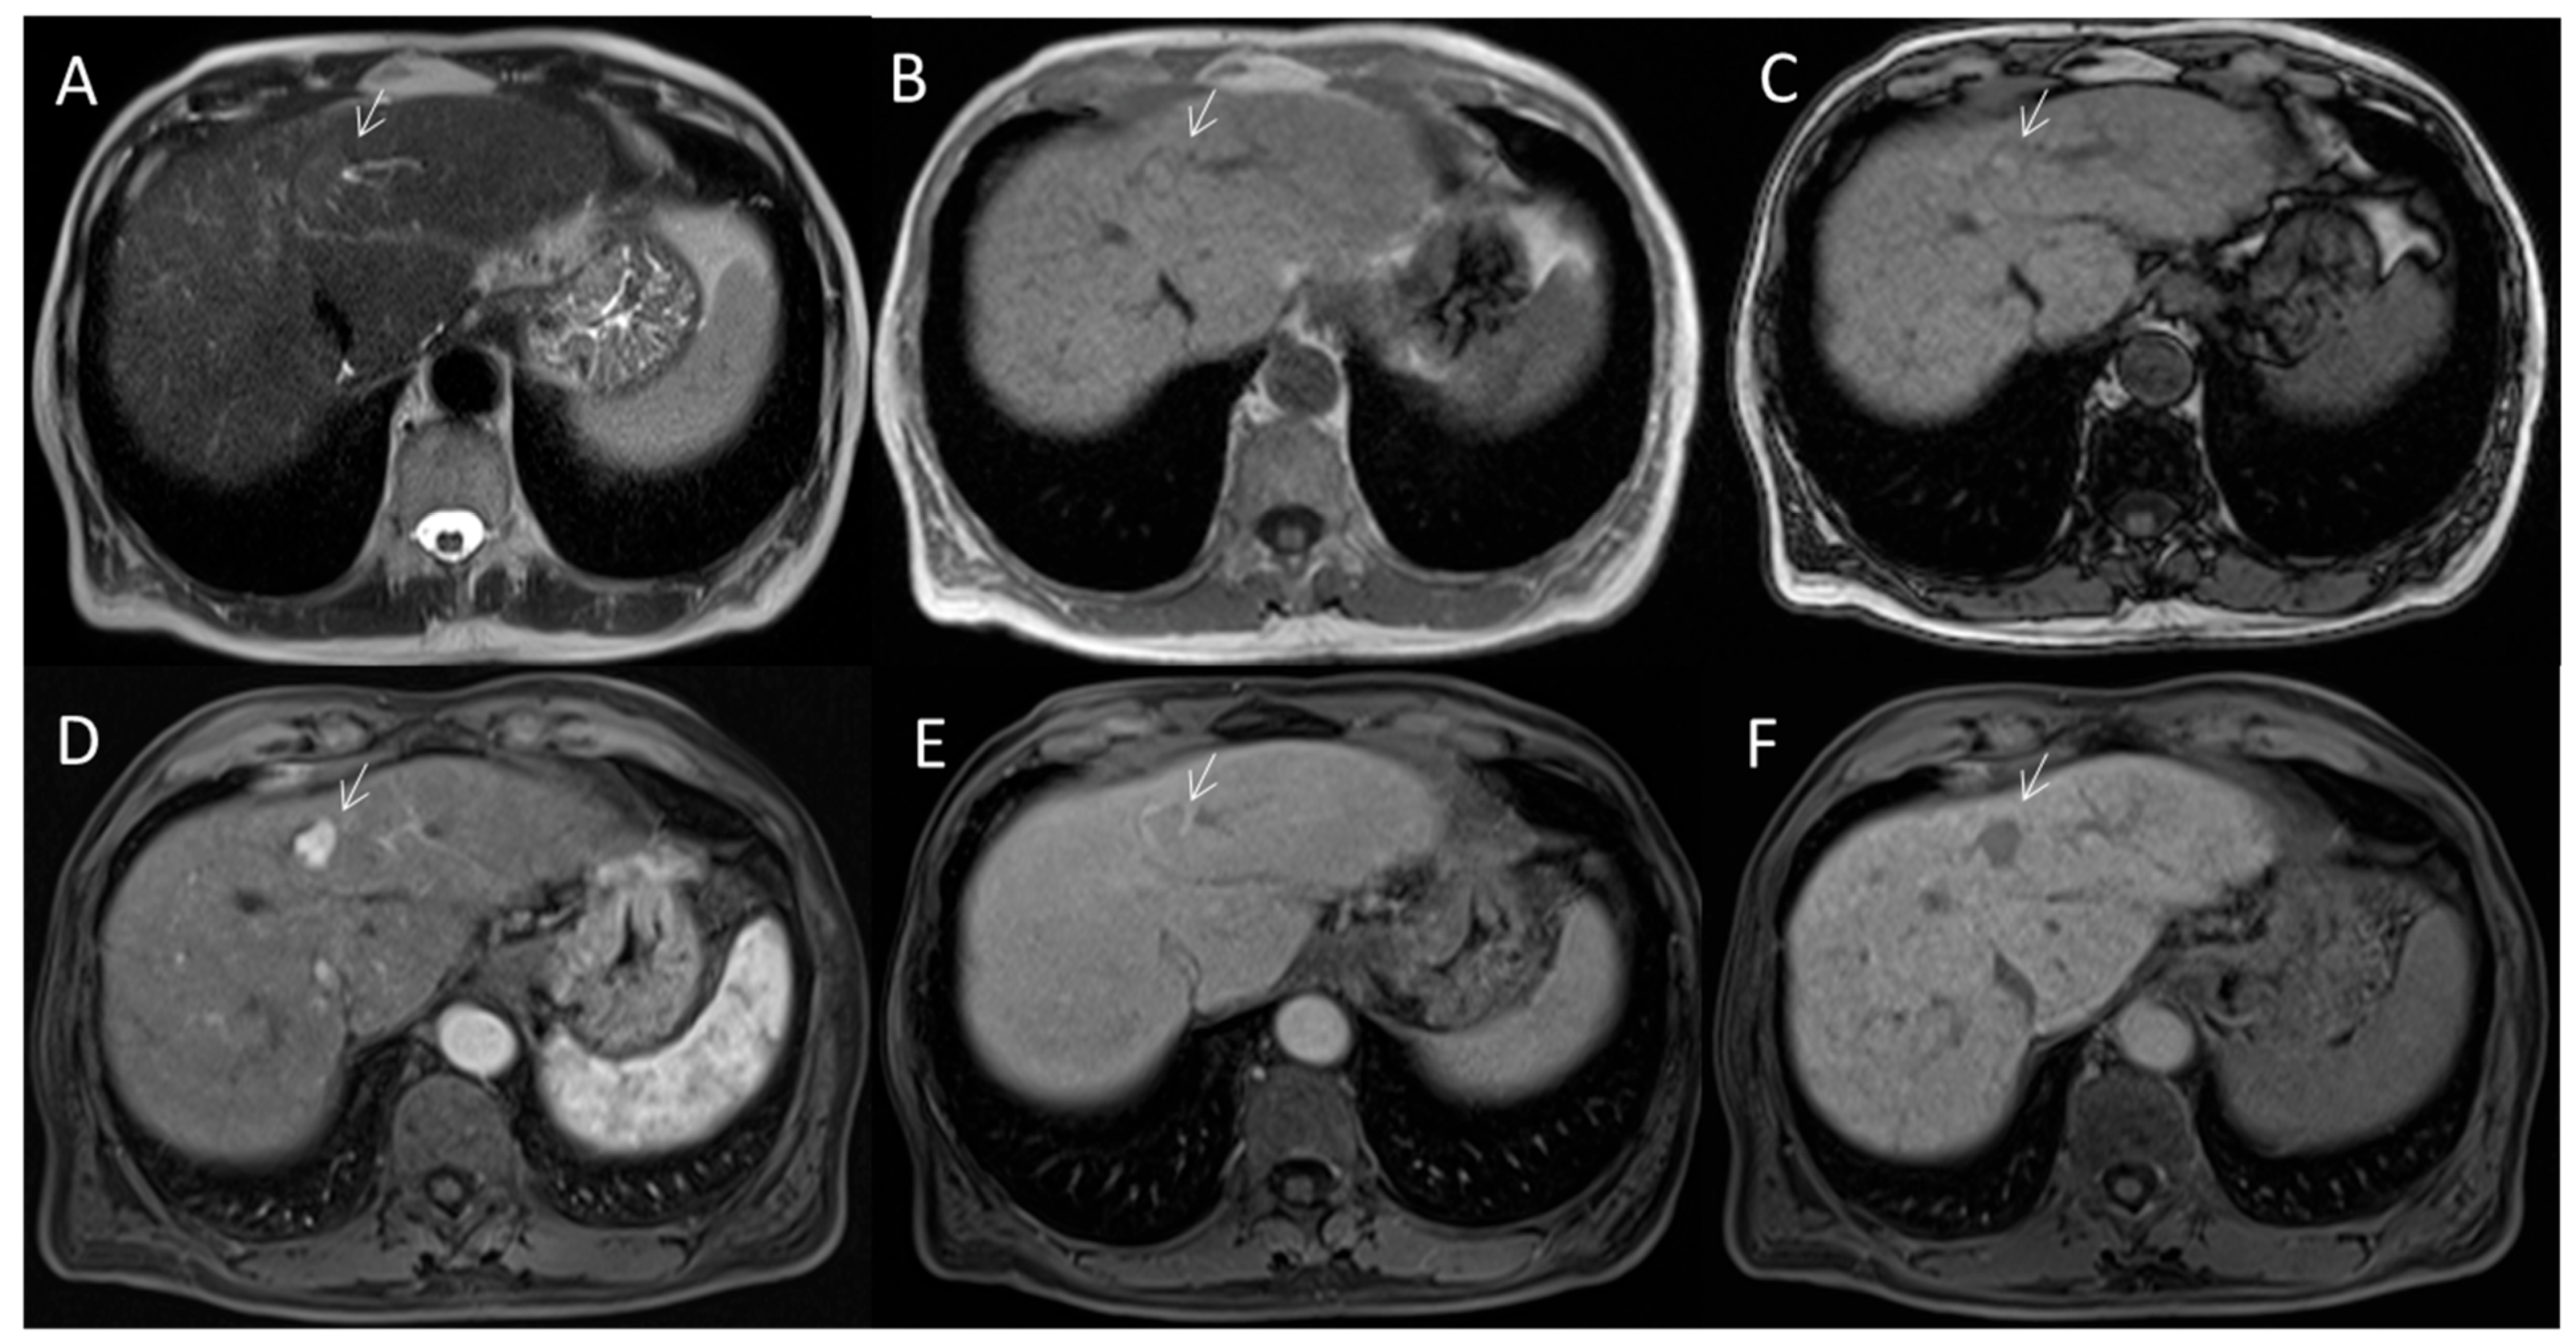

2.2.3. HCC Diagnosis

2.2.4. Ancillary Features

2.2.5. LR-M Category